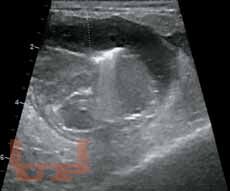

Книга восполняет острый дефицит в учебной литературе по УЗИ мелких домашних животных (кошек и собак). В ней систематизированы и стандартизированы УЗИ почек и мочевыводящих путей, печени и желчевыводящей системы, поджелудочной железы, желудочно-кишечного тракта, сосудистых аномалий брюшной полости (портосистемных шунтов и др.). Приведена методика обследования животных, критерии ультразвуковой нормы и патологии, которые могут быть использованы в протоколах и заключениях УЗИ.

Данное издание обобщает опыт отечественных и зарубежных специалистов. Представлены как собственные исследования авторов, так и материалы из иностранных источников. Текст сопровождается более чем 300 эхограммами.